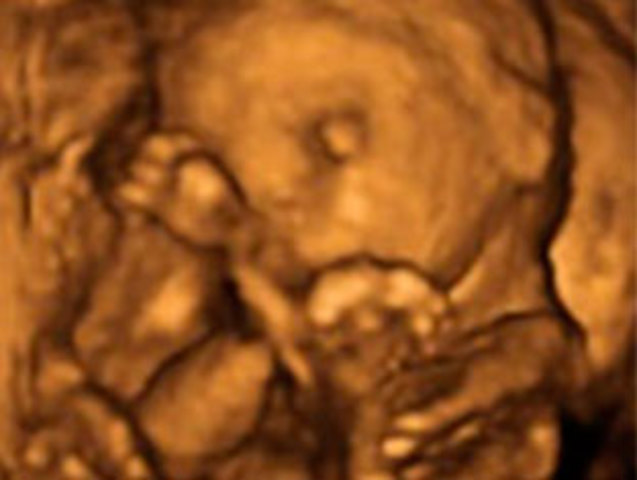

Los párpados del niño se abren y se pueden ver los ojos. La lengua sale de la boca y se mueve hacia los lados. Tu hijo bosteza, sonríe y empieza a hacer gestos como si de un niño mayor se tratase